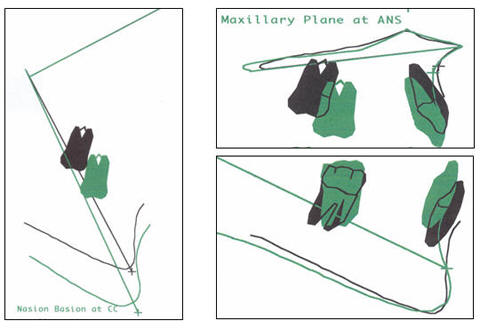

SOBREPOSICIÓN ANTES Y DESPUÉS DEL TRATAMIENTO |

Los trazos

cefalométrico antes y después del tratamiento como sus

correspondientes valores degún Ricketts, Jarabak y McNamara se

SUPERPOSICIONES

Son presentadas al

final adjunto a este trabajo